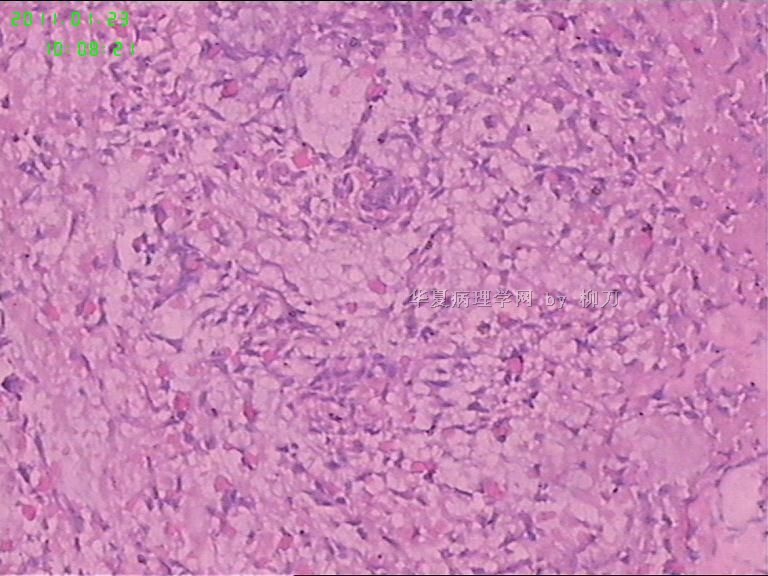

姓    名: ××× 性别:  男 年龄:  36

标本名称:  腮腺包块

简要病史:  包块2年多,数月来增大。

2,3图是前2个结节的镜下表现,梭形皮瓣是皮内痣。4以后是具完整包膜的肿块表现,核分裂少见。

我们考虑肌上皮瘤,少见多怪,老师们请多指教。

现有图像上看考虑肌上皮瘤。如果粘液样区域多,要考虑多形性腺瘤。

可以做一下组化:CK、SMA、S-100、GFAP、P63。

肌上皮瘤